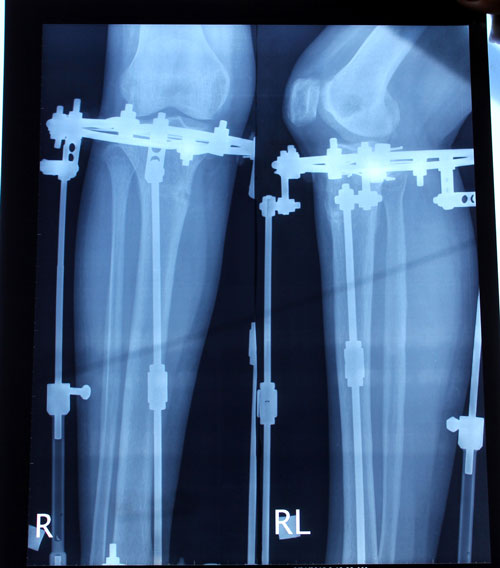

Рентген в 60 дней.

Рентген в 90 дней.

Приезжайте на снятие аппаратов!